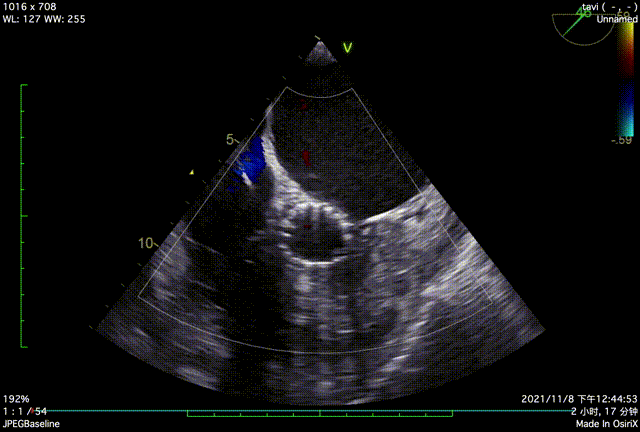

TTE